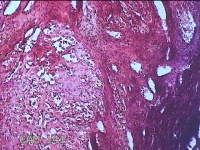

右卵巢囊肿

性别

女

年龄

23岁

临床诊断

一般病史

停经41天,下腹痛3天。

标本名称

大体所见

灰白暗红色囊性肿物3x1.8x0.8cm一个,表面糜烂,切开肿物,内见大量凝血块,囊壁厚约0.1cm。